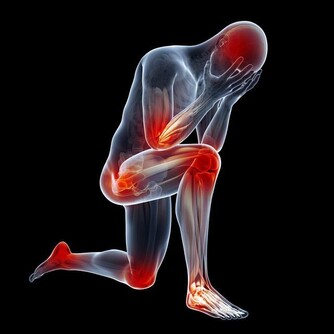

跟癌症、心腦血管疾病相比,關節炎似乎算不上多麼致命的疾患,然而它發作時的痛苦程度,讓所有患者一想起來就心有餘悸。想想手部、手腕、腳部關節疼痛、腫脹、僵硬的滋味吧,你一定不會喜歡的。

可是,如果已經罹患關節炎了,該怎麼辦呢?畢竟,患關節炎的人不在少數。這時候,我們需要做的就是減少關節炎發作的頻率,這不是不可能的。